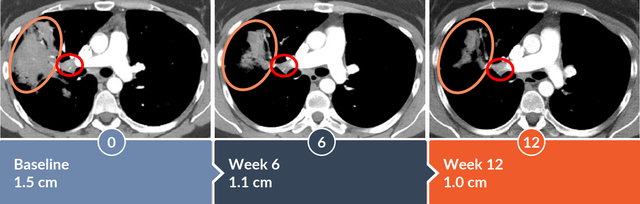

2022年9月,Alaunos Therapeutics在第六届国际癌症免疫治疗会议(CICON)中公布其TCR-T细胞疗法用于晚期非小细胞肺癌患者的病例报告。该患者在6周时达到部分缓解,目标病灶消退46.3%,12周时肿瘤病灶缩小51.2%。患者1为KRAS G12D突变的肺腺癌患者,既往接受手术、化疗、PD-L1抑制剂治疗等,病情进展后接受TCR-T治疗。TCR-T治疗6周后,右下叶肿瘤实现完全缓解(CR)。

TCR治疗12周后,右上肺叶肿瘤也从1.3cm缩小至1.0cm。